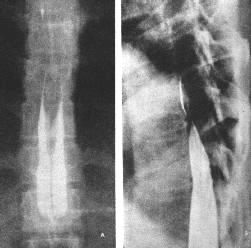

X線平片檢查約有30%~40%的患者可見骨質改變,在常規的脊柱正側位片及斜位片上,常見的徵象有:(1)椎間孔擴大或破壞;(2)椎管擴大,表現為椎弓根間距增寬;(3)椎體及附屬檔案的骨質改變,可見椎體骨質缺損、椎弓根破壞等;(4)椎管內鈣化,偶見於少數脊膜瘤,畸胎瘤及血管母細胞瘤;(5)椎旁軟組織陰影。由於椎管內腫瘤多為良性,早期X線片上常無骨質異常表現,有時僅在晚期可見椎弓根間距增寬,椎管壁皮質骨變薄椎管擴大等間接徵象。對於啞鈴形椎等內腫瘤,可見椎間孔擴大。X線片檢查,可排除脊柱畸形、腫瘤等原因造成的脊髓壓迫症,仍為一種不可缺少的常規檢查。